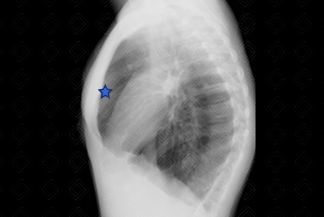

Texto alternativo para a imagem Figuras 1 e 2. Créditos: Dra. Elazir Mota - Rio de Janeiro/RJ

Descrição das figuras 1 e 2: Radiografia de tórax PA e perfil. Paciente do sexo feminino, 14 anos, com frequentes exacerbações da asma. Observa-se na radiografia alguns sinais de hiperinsuflação pulmonar, como coração em gota e aumento do espaço anteroposterior da caixa torácica, notadamente na região retroesternal (asterisco).

• Radiografia de tórax: O exame é normal na maioria dos casos. No entanto, nos casos mais graves e com exacerbações frequentes, pode-se observar: atelectasias, oligoemia periférica, espessamento de paredes brônquicas e sinais de hiperinsuflação pulmonar (como nas imagens acima);